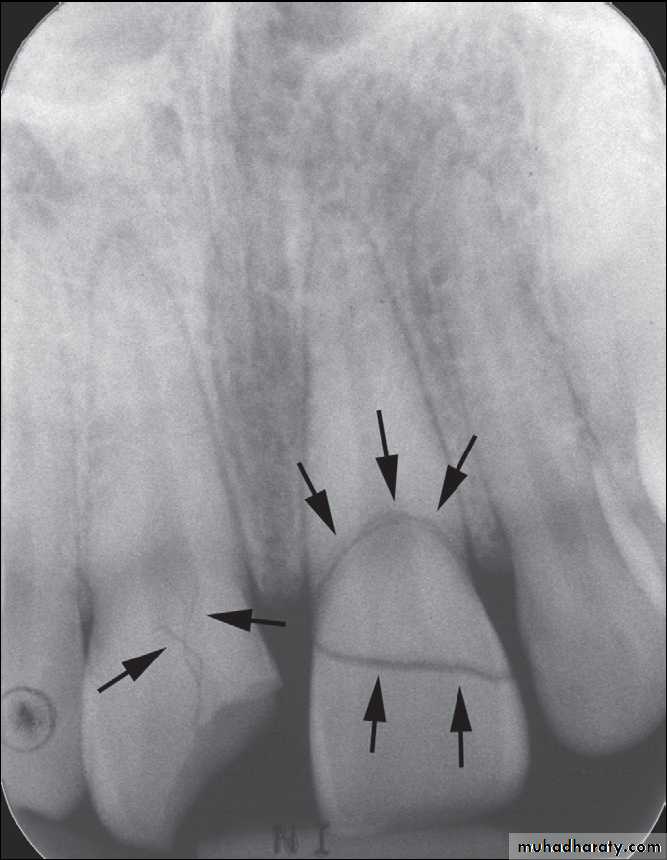

Incisors with crown-root fractures

Injuries to supporting bone- Comminution of both alveolar cortices

Often with intrusive or lateral luxation- Fracture of a single cortex

Buccal or lingual cortex fracture

- Fracture of alveolar process en bloc

Fracture may or may not propagate through socket, may contain 1 or multiple teeth but underlying maxilla or mandible grossly stable